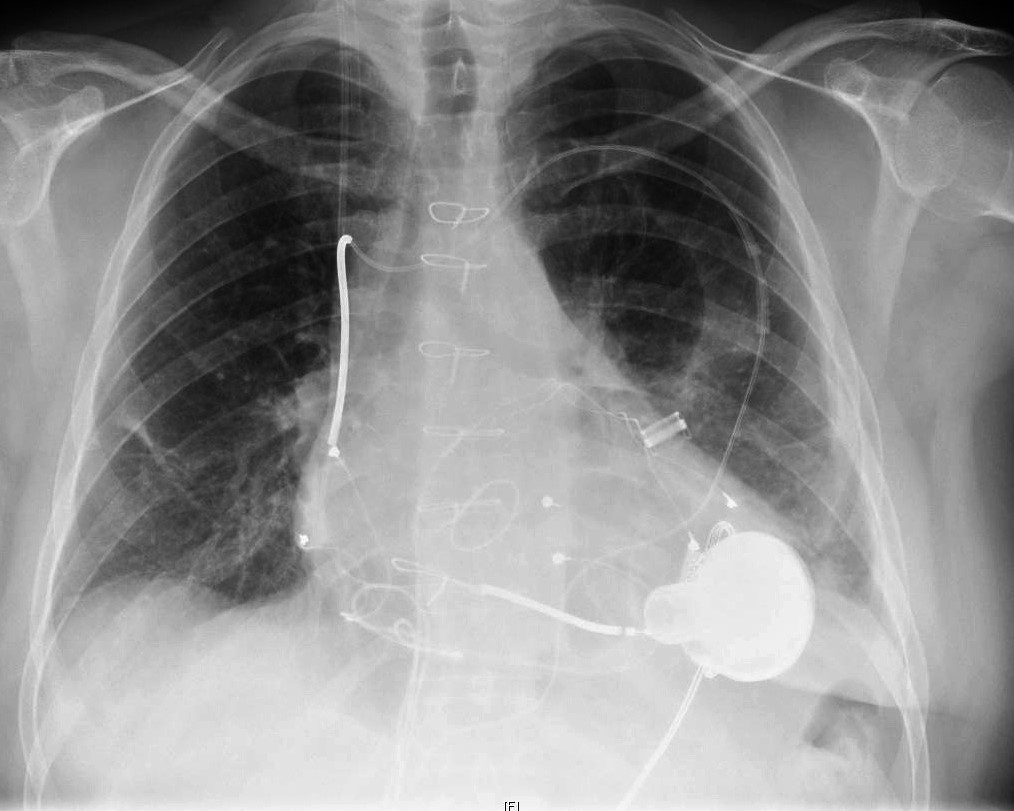

В 1963 году Майкл успешно имплантировал вспомогательное устройство левого желудочка (LVAD) пациенту с тяжелой сердечной недостаточностью. Это механический насос, имплантированный в грудь, помогающий перекачивать кровь от желудочка к остальному телу. LVAD был разработан, чтобы позволить желудочку отдохнуть и восстановиться.

Подытоживая, VAD используют, чтобы помочь сердцу работать в ожидании других методов лечения, например трансплантации сердца. В некоторых случаях VAD используется для постоянной помощи сердцу перекачивать кровь. Чаще всего устройство размещают в левом желудочке (LVAD).